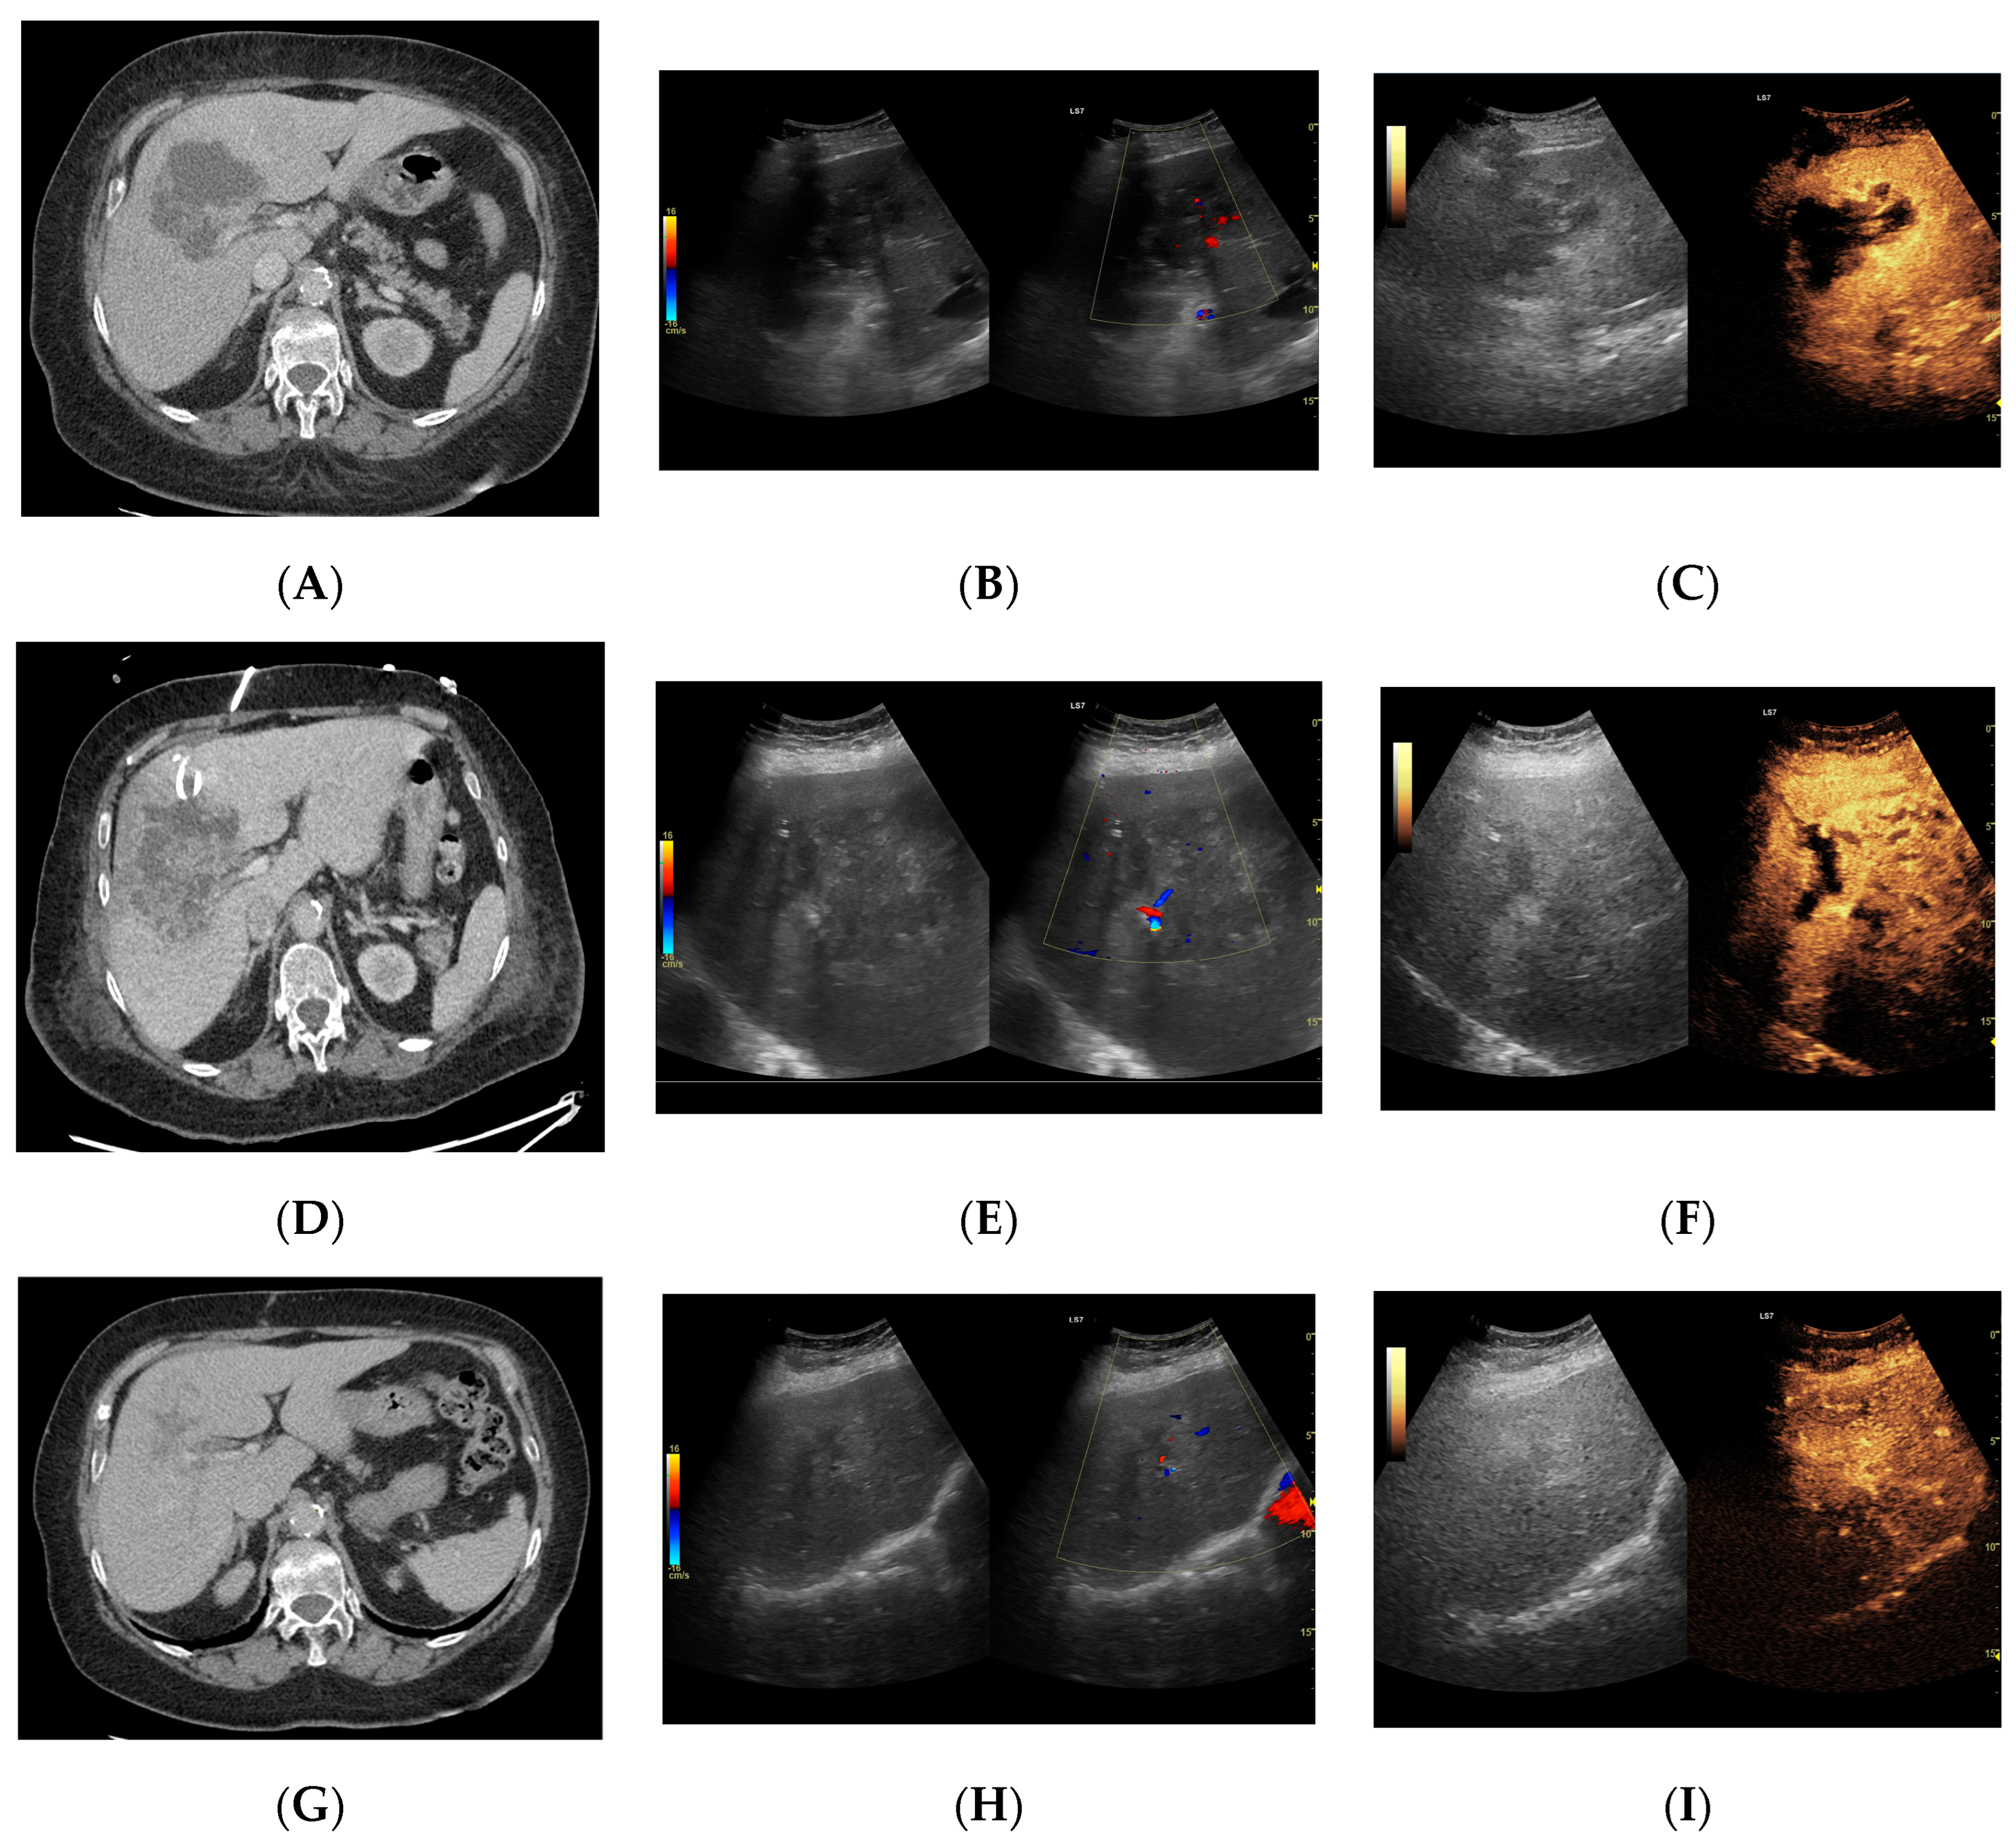

Utility of Contrast-Enhanced Ultrasound in Optimizing Hepatic Abscess Treatment and Monitoring

3. Results

3.2.1. Arterial Phase

3.2.2. Early Venous Phase

3.2.3. Late Venous Phase